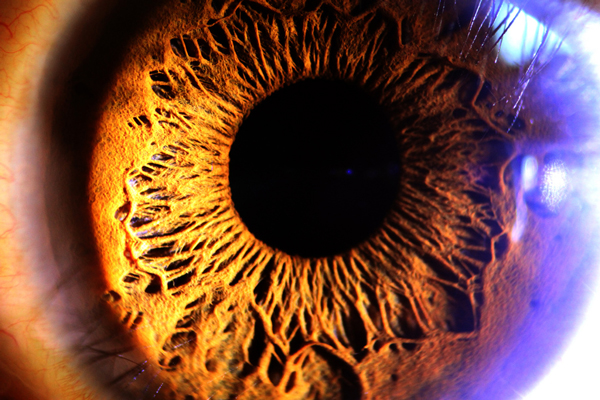

UYGULAMA İLE KATARAKT KONTROLÜ

"Portatif Göz Tetkik Kiti" adı verilen uygulama, akıllı telefonun kamerasıyla göz merceğini tarayarak kataraktı ortaya çıkarıyor. Uygulamada hipermetrop, miyop ve astigmatın teşhisi içinse ekranda giderek küçülen harfler kullanılıyor. Uygulama, kameranın flaşını kullanarak da gözün arkasını kontrol ederek optik sinirlerdeki olası bozuklukları ortaya çıkarıyor.

Dünyada hipermetrop, miyop, astigmat, glokom, katarakt gibi görme bozukluklarından muzdarip 285 milyondan fazla kişi bulunuyor.